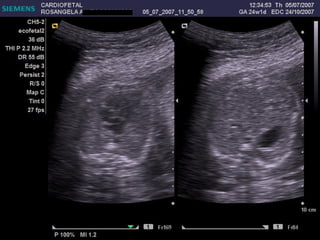

Cámaras COLUMNA AORTA ESTERNON VP VP BANDA MODERADORA FLAP VI VD AI AD

EXAMEN BASICO VENTRICULOS Tamaños Paredes Banda moderadora Tabique

Tamaño

Paredes

Banda moderadora

Tabique